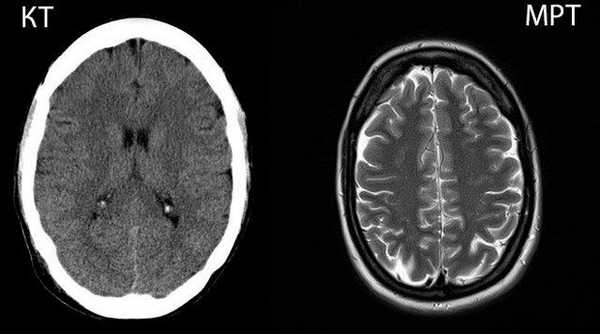

КТ и МРТ: в чем отличия и что лучше?

Компьютерная и магнитно-резонансная томографии — это современные информативные диагностические процедуры, которые позволяют с высокой степенью точности и детализации визуализировать внутренние структуры организма. Оба метода предполагают получение послойных снимков интересующей зоны в разных плоскостях. Основное, чем отличается КТ от МРТ – это принцип сканирования. Методы основаны на разных технологиях и применяются в различных клинических ситуациях. Исходя из задач диагностики, лечащий врач определяет, что лучше — КТ или МРТ, а затем назначает наиболее рациональный метод диагностики для конкретного случая.

Принцип действия КТ и МРТ: в чем разница

Компьютерная и магнитно-резонансная томография относятся к лучевым методам диагностики. Основное отличие КТ от МРТ заключается в технологии воздействия на организм с целью получения изображения.

Компьютерная томография использует ионизирующее излучение (рентген-сканирование). Метод базируется на способности тканей организма в различной мере задерживать рентгеновские лучи. При прохождении сквозь интересующую область лучи максимально поглощаются плотными тканями (например, костями) и легко проникают сквозь мягкотканные элементы. В результате на снимках хорошо визуализируются кости и другие плотные структуры - конкременты, инородные тела.

Отличие компьютерной томографии от стандартной рентгенографии — в количестве получаемых снимков. В ходе КТ вокруг пациента вращается трубка, которая посылает лучи, а специальные датчики их улавливают. В результате процедуры получают пошаговые рентгеновские снимки зоны исследования. Чем чаще вращается трубка, тем меньше шаг сканирования, и, соответственно, выше разрешающая способность.

МР-томография базируется на явлении ядерно-магнитного резонанса, свойственного атомам водорода, содержащимся в молекулах воды. Больше всего воды присутствует в мягких тканях. Ткани, которые содержат мало воды (например, кости), визуализируются плохо. Датчик томографа регистрирует изменения состояния атомов водорода под воздействием радиоизлучения в постоянном магнитном поле.

В результате получают пошаговые снимки в трех плоскостях, на которых видны мягкотканные структуры организма.

Понимая, в чем состоит разница между КТ и МРТ, можно сделать логический вывод о большей информативности процедуры относительно тех или иных видов тканей. Однако диагностические возможности методов можно расширить с помощью контрастных веществ. При КТ применяют йодсодержащий контраст, который распределяется в организме с током крови и делает видимыми сосуды и некоторые мягкие ткани. Это позволяет в ряде случаев применять КТ для исследования внутренних органов, новообразований и сосудов.